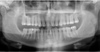

Le cliché panoramique révèle une perte osseuse discrète.

Le cliché panoramique de fin de traitement montre la nouvelle position des dents et un parodonte sain.